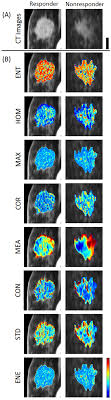

A ct scan is one of the most frequently utilized exams to detect cancer and to show things such as a tumor's shape and size.

Before a pet/ct scan, an iv that injects a small amount of a radioactive substance will be placed into one of your veins. It also helps doctors predict how well you will recover.find the right place for a biopsy.plan A pelvic ct scan can be used to detect several types of cancer. When the doctor knows this, they can choose the best course of treatment and maybe even predict your chances of recovery. The scan lets them:learn the cancer's stage. However, they are also scanning my thorax. I performed an scope examination of her esophagus and confronted a huge cancer occupying the lower portion of her esophagus. A ct scan can help detect a wide range of abnormalities or disease, including cancer, in any part of the body. Each picture created during a ct procedure. Further, its diagnostic reach can go beyond the bone. You are encouraged to drink clear liquids. Do ct scans detect breast cancer? Learn more about it on our blog.

Ct scans can help doctors: If you have a large breast cancer, your doctor may order a ct scan to assess whether or not the cancer has moved into the chest wall. This substance is often called a tracer, because it helps reveal cancer in the body. The scan lets them:learn the cancer's stage. Computed tomography scan, ct scan, cat scan, and spiral or helical ct. 234 views answered >2 years ago Before the scan, you will either drink a liquid dye or be given an injection of dye into a vein in your arm. Breast cancer affects over 200,000 women each year. A pelvic ct scan can be used to detect several types of cancer. Contrast medium is a dye that helps body tissues show up more clearly on the scan. In contrast with bone scans, which are only able to detect bone metastases, pet/ct has the advantage of concurrently imaging other common sites of breast cancer metastases such as the liver and lungs, says lead author patrick morris, a breast cancer specialist at memorial sloan kettering. You are encouraged to drink clear liquids. This helps determine whether or not the cancer can be removed with mastectomy.